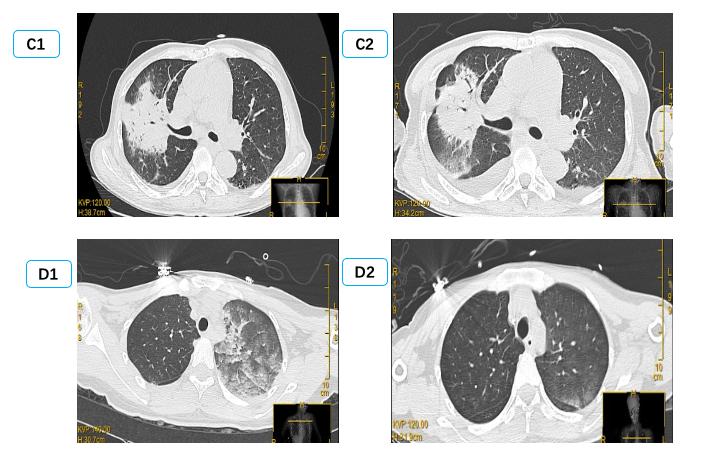

由于单侧PE病情轻重不一,影像表现可以为间质B线、毛玻璃影,严重可表现为肺实变,因此常误诊为肺部感染、肺出血、支气管扩张、肺实变等[29-31]导致病情延误。本研究中有12例单侧PE患者初次影像报告未准确识别; 因此建立重复可量化的单侧PE影像定义及分级标准有组于单侧PE诊断[32]。有心脏病史,心脏超声提示长期二尖瓣反流,长期有右侧胸腔积液,结合入院后床边BNP及肺部超声可以进行鉴别,尤其是床边重症超声可以及时发现明显二尖瓣反流,及时监测肺部超声表现可予以鉴别诊断。如图 4中B患者,入院前肺部CT正常,因失血性休克导致心脏骤停3 h后胸片提示右侧渗出加重,肺部超声由A线为主逐渐发展为B7线、B3线、融合B线及肺实变,提示患者PE程度逐渐加重; 同时心脏超声提示新发重度二尖瓣反流,综合考虑诊断单侧PE,经呼吸支持,利尿治疗后患者胸片、肺部超声均迅速恢复正常。而长期心衰合并二尖瓣反流患者,联合下腔静脉、颈静脉等超声进行容量评估,可与肺部感染相鉴别[33]。急性胸痛患者肌酸激酶同工酶联合床边及时检测肌钙蛋白,可早期诊断心肌梗死,为诊断心源性PE提供依据,本研究中两组间心肌损伤标志物差异无统计学意义。

| 图 4 患者B胸片及肺部超声改变过程 Fig 4 X-ray and lung ultrasound image of patient B |

单侧PE临床表现差异大,轻者无症状,严重者表现为顽固性低氧血症,需要呼吸机辅助。肺超评分、左心室充盈压和肺动脉收缩压是无创正压通气治疗失败的独立危险因素,尽早识别需要有创辅助通气患者,避免治疗延误[34]。但严重单侧PE由于双侧肺顺应性不一致,为改善氧合提高呼气末正压、增加潮气量,可导致正常一侧肺过度通气,增加肺循环阻力,同时导致更多肺血流进入患侧肺部,全肺通气/血流不一致加重,因此单肺机械通气可能适于单侧PE治疗。研究显示单侧PE分级越高,机械通气时间更长,氧合指数更低[32],但本试验中氧合指数单侧PE和双侧PE组间差异不明显,可能与部分患者症状轻,以及单侧PE组更多使用呼吸机辅助有关。约1.95%~8.3%患者需要体外膜肺支持[4-5],尤其是在心脏术后及心脏骤停后迅速发生的单侧PE。本次研究中无单侧PE行体外膜肺,但有71.4%(10例)患者需要呼吸机支持,其中部分患者病情进展迅速,如图中B患者。呼吸支持是维持单侧PE氧合的关键,但原发病处理如严重二尖瓣脱垂、肺静脉堵塞等手术处理等是单侧PE治疗前提,图中A、B、D、E患者因心脏骤停诱发单侧PE,及时心肺复苏恢复自主循环,全身及冠脉血供稳定后患者单侧PE完全消失; 图中C患者严重器质性二尖瓣反流未处理单侧PE持续无缓解。